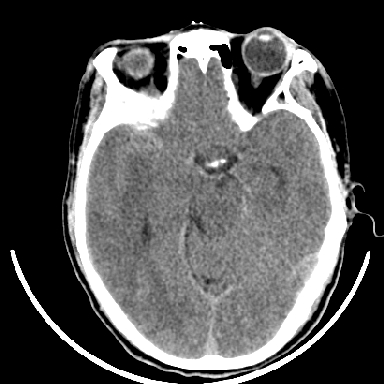

胶质母细胞瘤可能性大

瘤卒中

支持胶质瘤并出血

以下是引用林林林在2007-1-13 19:06:00的发言:[br]支持胶质瘤并出血